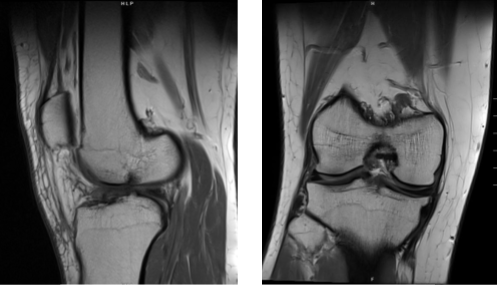

MRI were reviewed and discussed; the Linear signal elevation is identified within the posterior hom of the medial meniscus on coronal sequence image #12 and sagittal sequence image #26 associated with intrasubstance tears. Tear within the lateral meniscus is not appreciated.

Preservation of joint space height is noted in both medial and lateral femorotibial compartments. Intermediate signal intensity is noted in association with the anterior cruciate ligament suggestive of sprain.

There is no evidence of discontinuity or retraction of the posterior cruciate ligament to indicate tear. There is no evidence of tear of the medial collateral ligament. There is no evidence of tearing of the lateral collateral ligament.

There is no evidence of tearing of the quadriceps tendon. There is no evidence of tearing of the patellar tendon. There is no evidence of tear of the medial or lateral patellar retinaculum. Popliteus peritendinous fluid associated with tenosynovitis.

Semimembranosus and semitendinosus peritendinous fluid is also associated with tenosynovitis. There is no evidence of signal changes associated with the iliotibial band. There is no evidence of degenerative changes of the proximal tibiofemoral articulation.

Mild joint effusion is noted with both suprapatellar and infrapatellar components. There is no evidence of Baker’s cyst posterior to the medial femoral condyle. There is no evidence of chondromalacia within the posterior patella.

Tibial tubercle to trochlear groove distance measures approximately 5 mm within normal limits. Trace anterior soft tissue edema is noted. There is no evidence of bone marrow signal change to indicate fracture, avascular necrosis, osteomyelitis or bone marrow replacement process.

Impression: Intrasubstance tear posterior horn of the medial meniscus. Anterior cruciate ligament sprain. Popliteus, semimembranosus, and semitendinosus tenosynovitis and mild effusion. Which means that the MRI results showed medial meniscus tear and tearing of the ACL.

Magnetic resonance imaging scan of the right knee